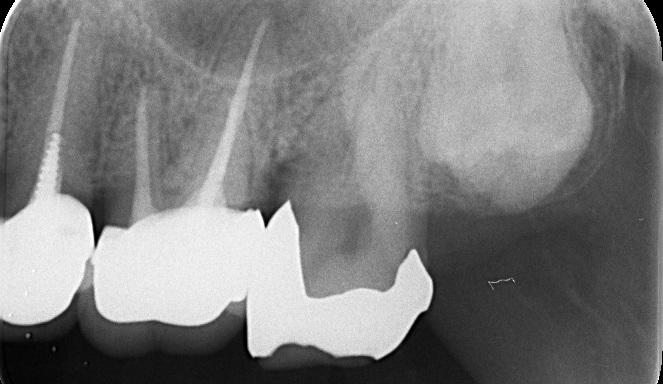

“実際の実施例1”

この患者様は、口腔内全体において重度の歯周病が生じており、歯磨き指導、クリーニング、Flap手術等を行ったが、歯周ポケットが深すぎるため

ブルーラジカル適用症例と診断し、施術を行いました。

(実施前)

施術前のレントゲンと口腔内写真です。施術前にプラークの除去を行ってから、施術します。